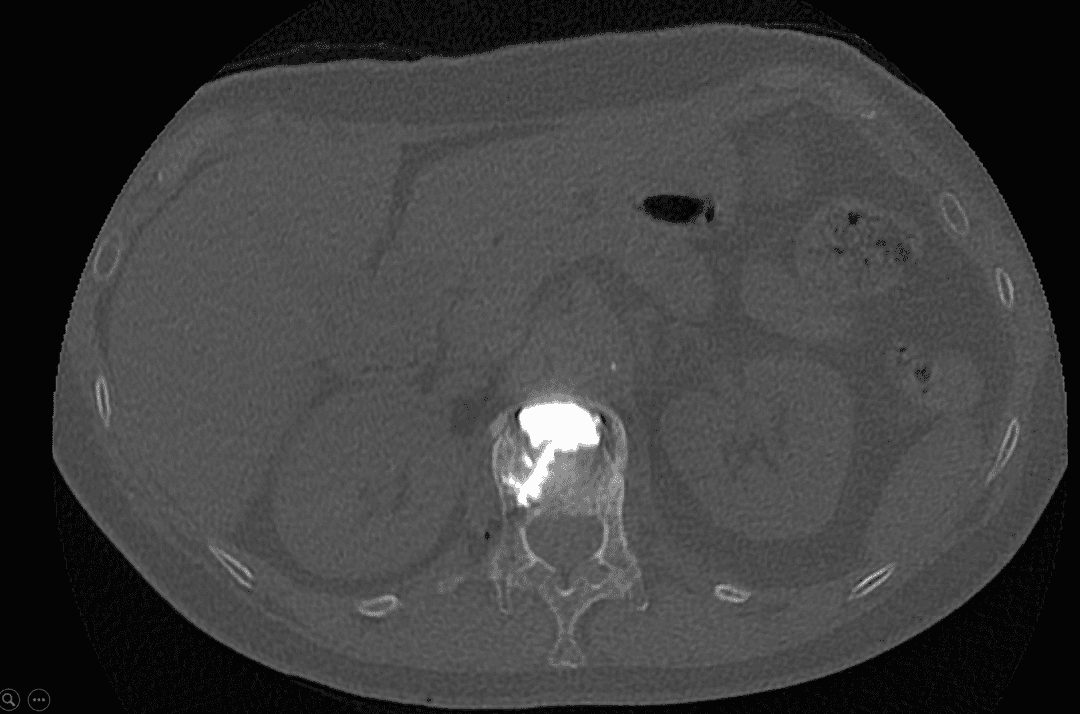

Résultat après injection de ciment

Injection du ciment

Une fois l’aiguille positionnée correctement, le ciment acrylique est injecté de façon contrôlée. Cette étape cruciale, suivie en continu grâce aux images, garantit une distribution homogène du ciment tout en minimisant le risque de fuite hors du vertèbre.